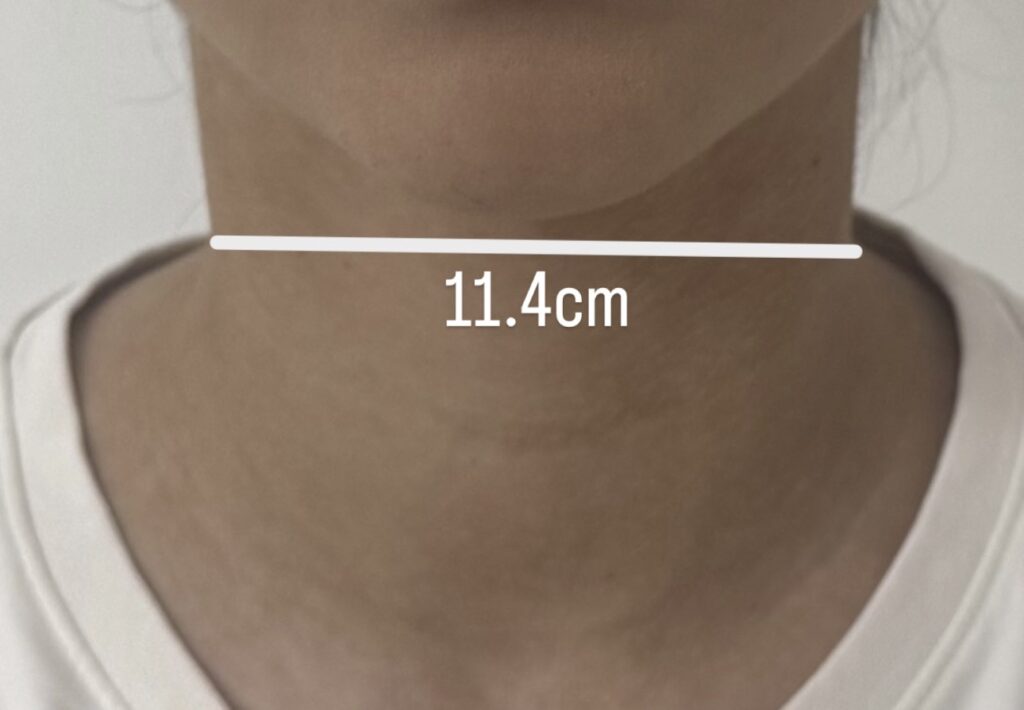

U trećoj fazi istraživanja fokus je bio na primeni prethodno ispitanih metoda na razvoj personalizovane vratne ortoze. Cilj ove faze bio je formiranje ortoze koja prati anatomiju vrata, omogućava lakše postavljanje na telo i može fizički da se realizuje korišćenjem...

U drugoj fazi istraživanja fokus je bio na proveri metoda parametarskog modelovanja i razvijanja površi kroz jednostavniji primer modela ruke, pre njihove primene na složenijoj formi vratne ortoze. Kao osnova korišćen je postojeći 3D model ruke, koji je skaliran prema...

Oblast istraživanja Ergonomska i funkcionalna optimizacija pomagala za imobilizaciju vratne kičme sa fokusom na personalizaciju putem digitalnih tehnologija i samostalnu upotrebu. Tema istraživanja Dizajn i razvoj personalizovane modularne vratne kragne zasnovane na digitalnom modelovanju i unapređenim ergonomskim karakteristikama. Stanje u...